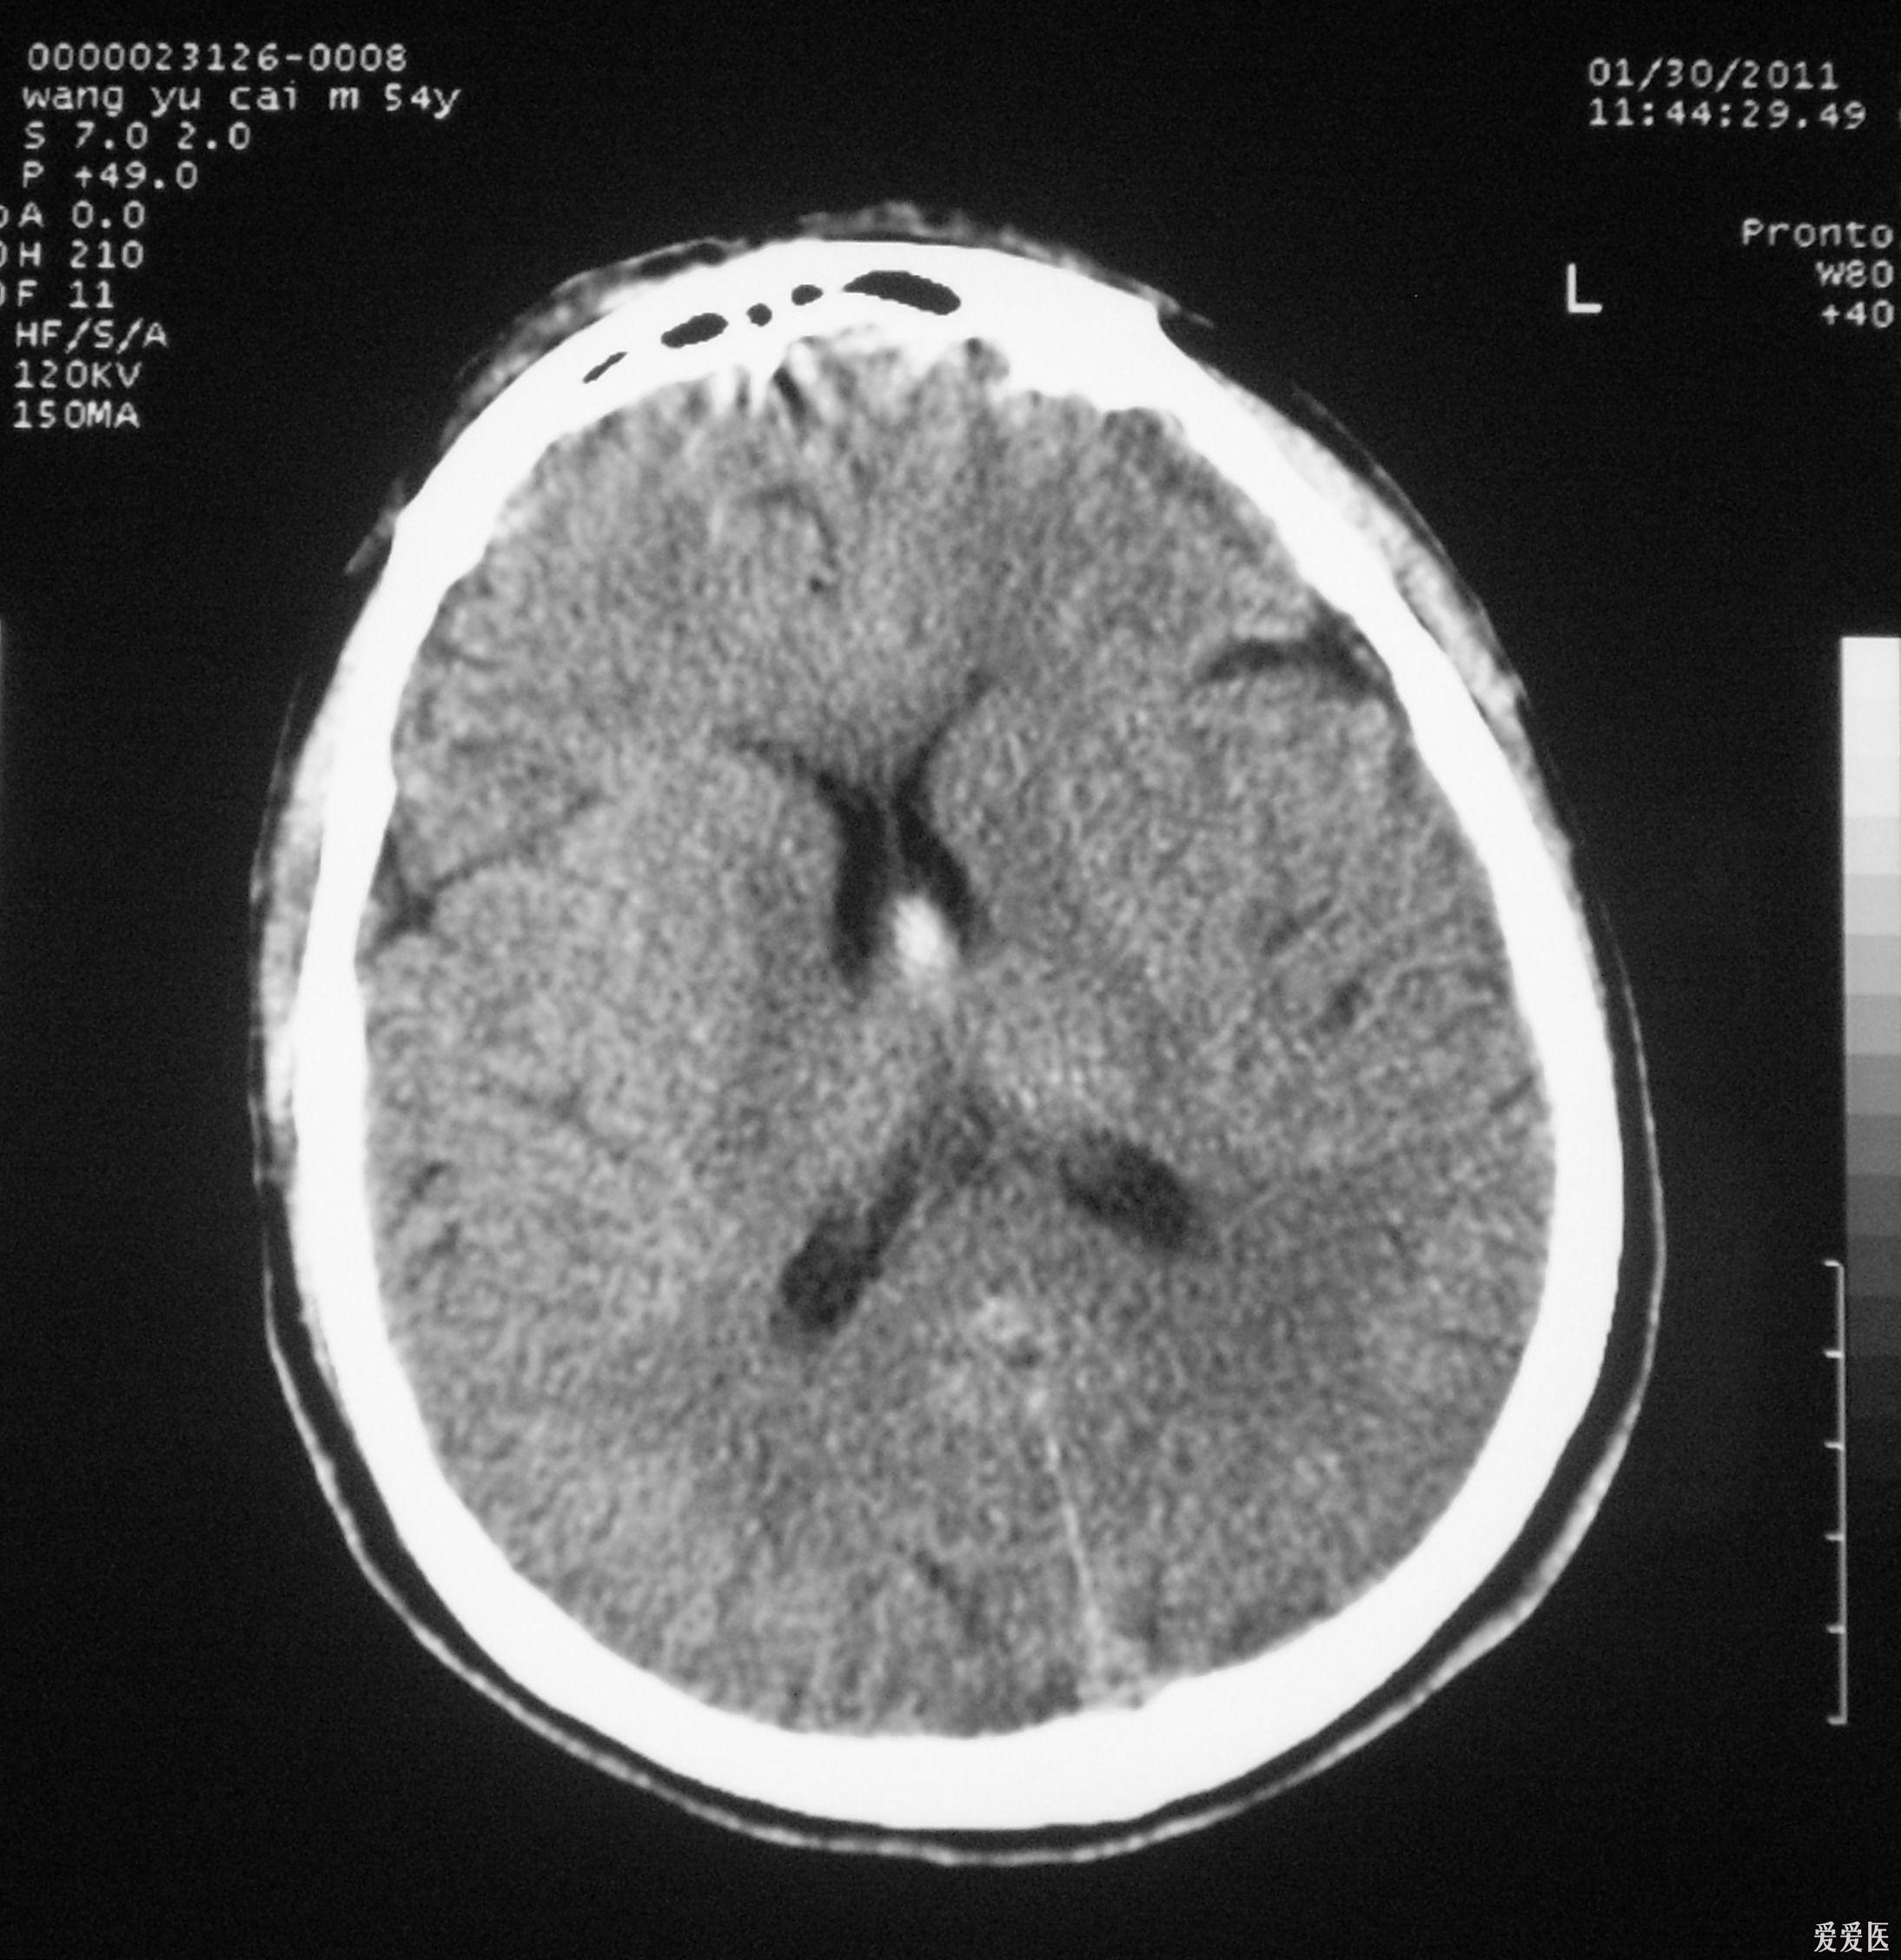

头部ct提示蛛网膜下腔出血

头ct提示自发性蛛网膜下腔出血